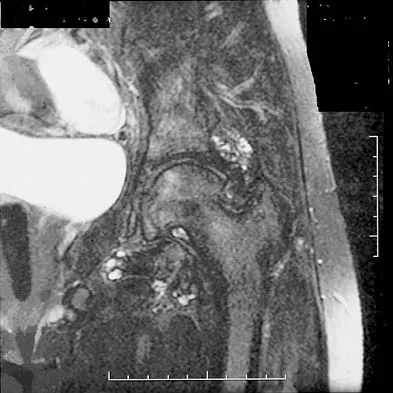

Figures 1a through 1c show the radiograph and MRI scans of a 16-year-old patient who has a painful hip. Examination reveals a significant limp, limited abduction and internal rotation, and severe pain with internal rotation and adduction. A biopsy specimen is shown in Figure 1d. What is the deposited pigment observed in this condition?

Explanation

Pigmented villonodular synovitis (PVNS) is a synovial proliferative disorder that remains a diagnostic difficulty. The most common clinical features are mechanical pain and limited joint motion. On radiographs, the classic finding is often a large lesion, associated with multiple lucencies. Other findings may include a normal radiographic appearance, loss of joint space, osteonecrosis of the femoral head, or acetabular protrusion. MRI is the imaging modality of choice and will show the characteristic findings of a joint effusion, synovial proliferation, and bulging of the hip. The synovial lining has a low signal on T1- and T2-weighted images, secondary to hemosiderin deposition. Copper deposition occurs in patients with Wilson's disease, which mainly affects the liver. Bhimani MA, Wenz JF, Frassica FJ: Pigmented villonodular synovitis: Keys to early diagnosis. Clin Orthop 2001;386:197-202.